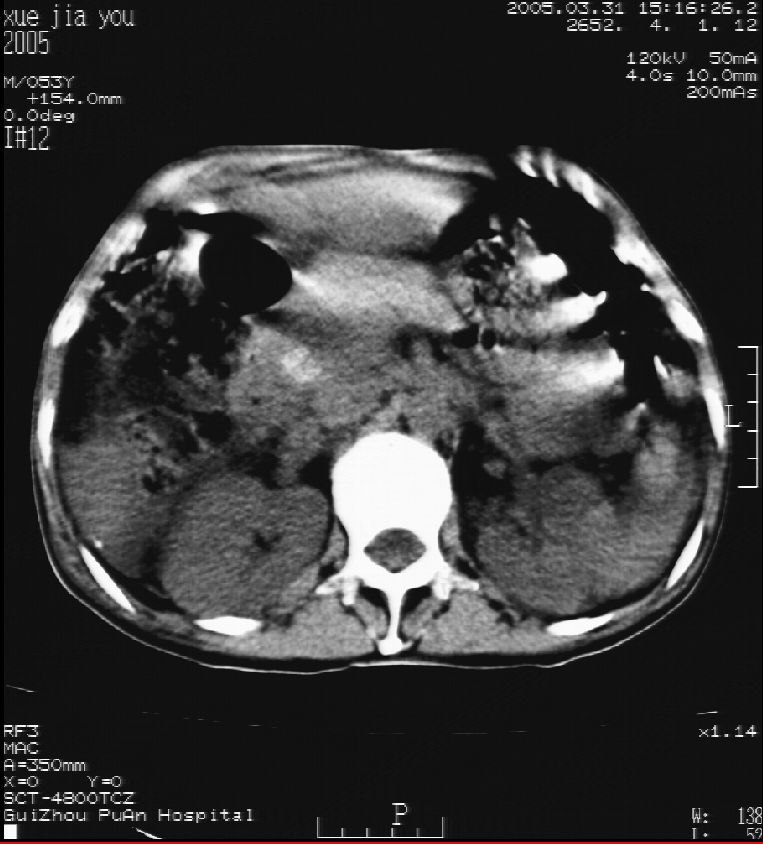

男 55岁  反复上腹痛1年,伴恶心呕吐。2005年做第一次检查后,到外院做b超检查提示肝囊肿,未做任何手术。2006年做过胆总管结石术。骨窗未见异常

2007年8月片